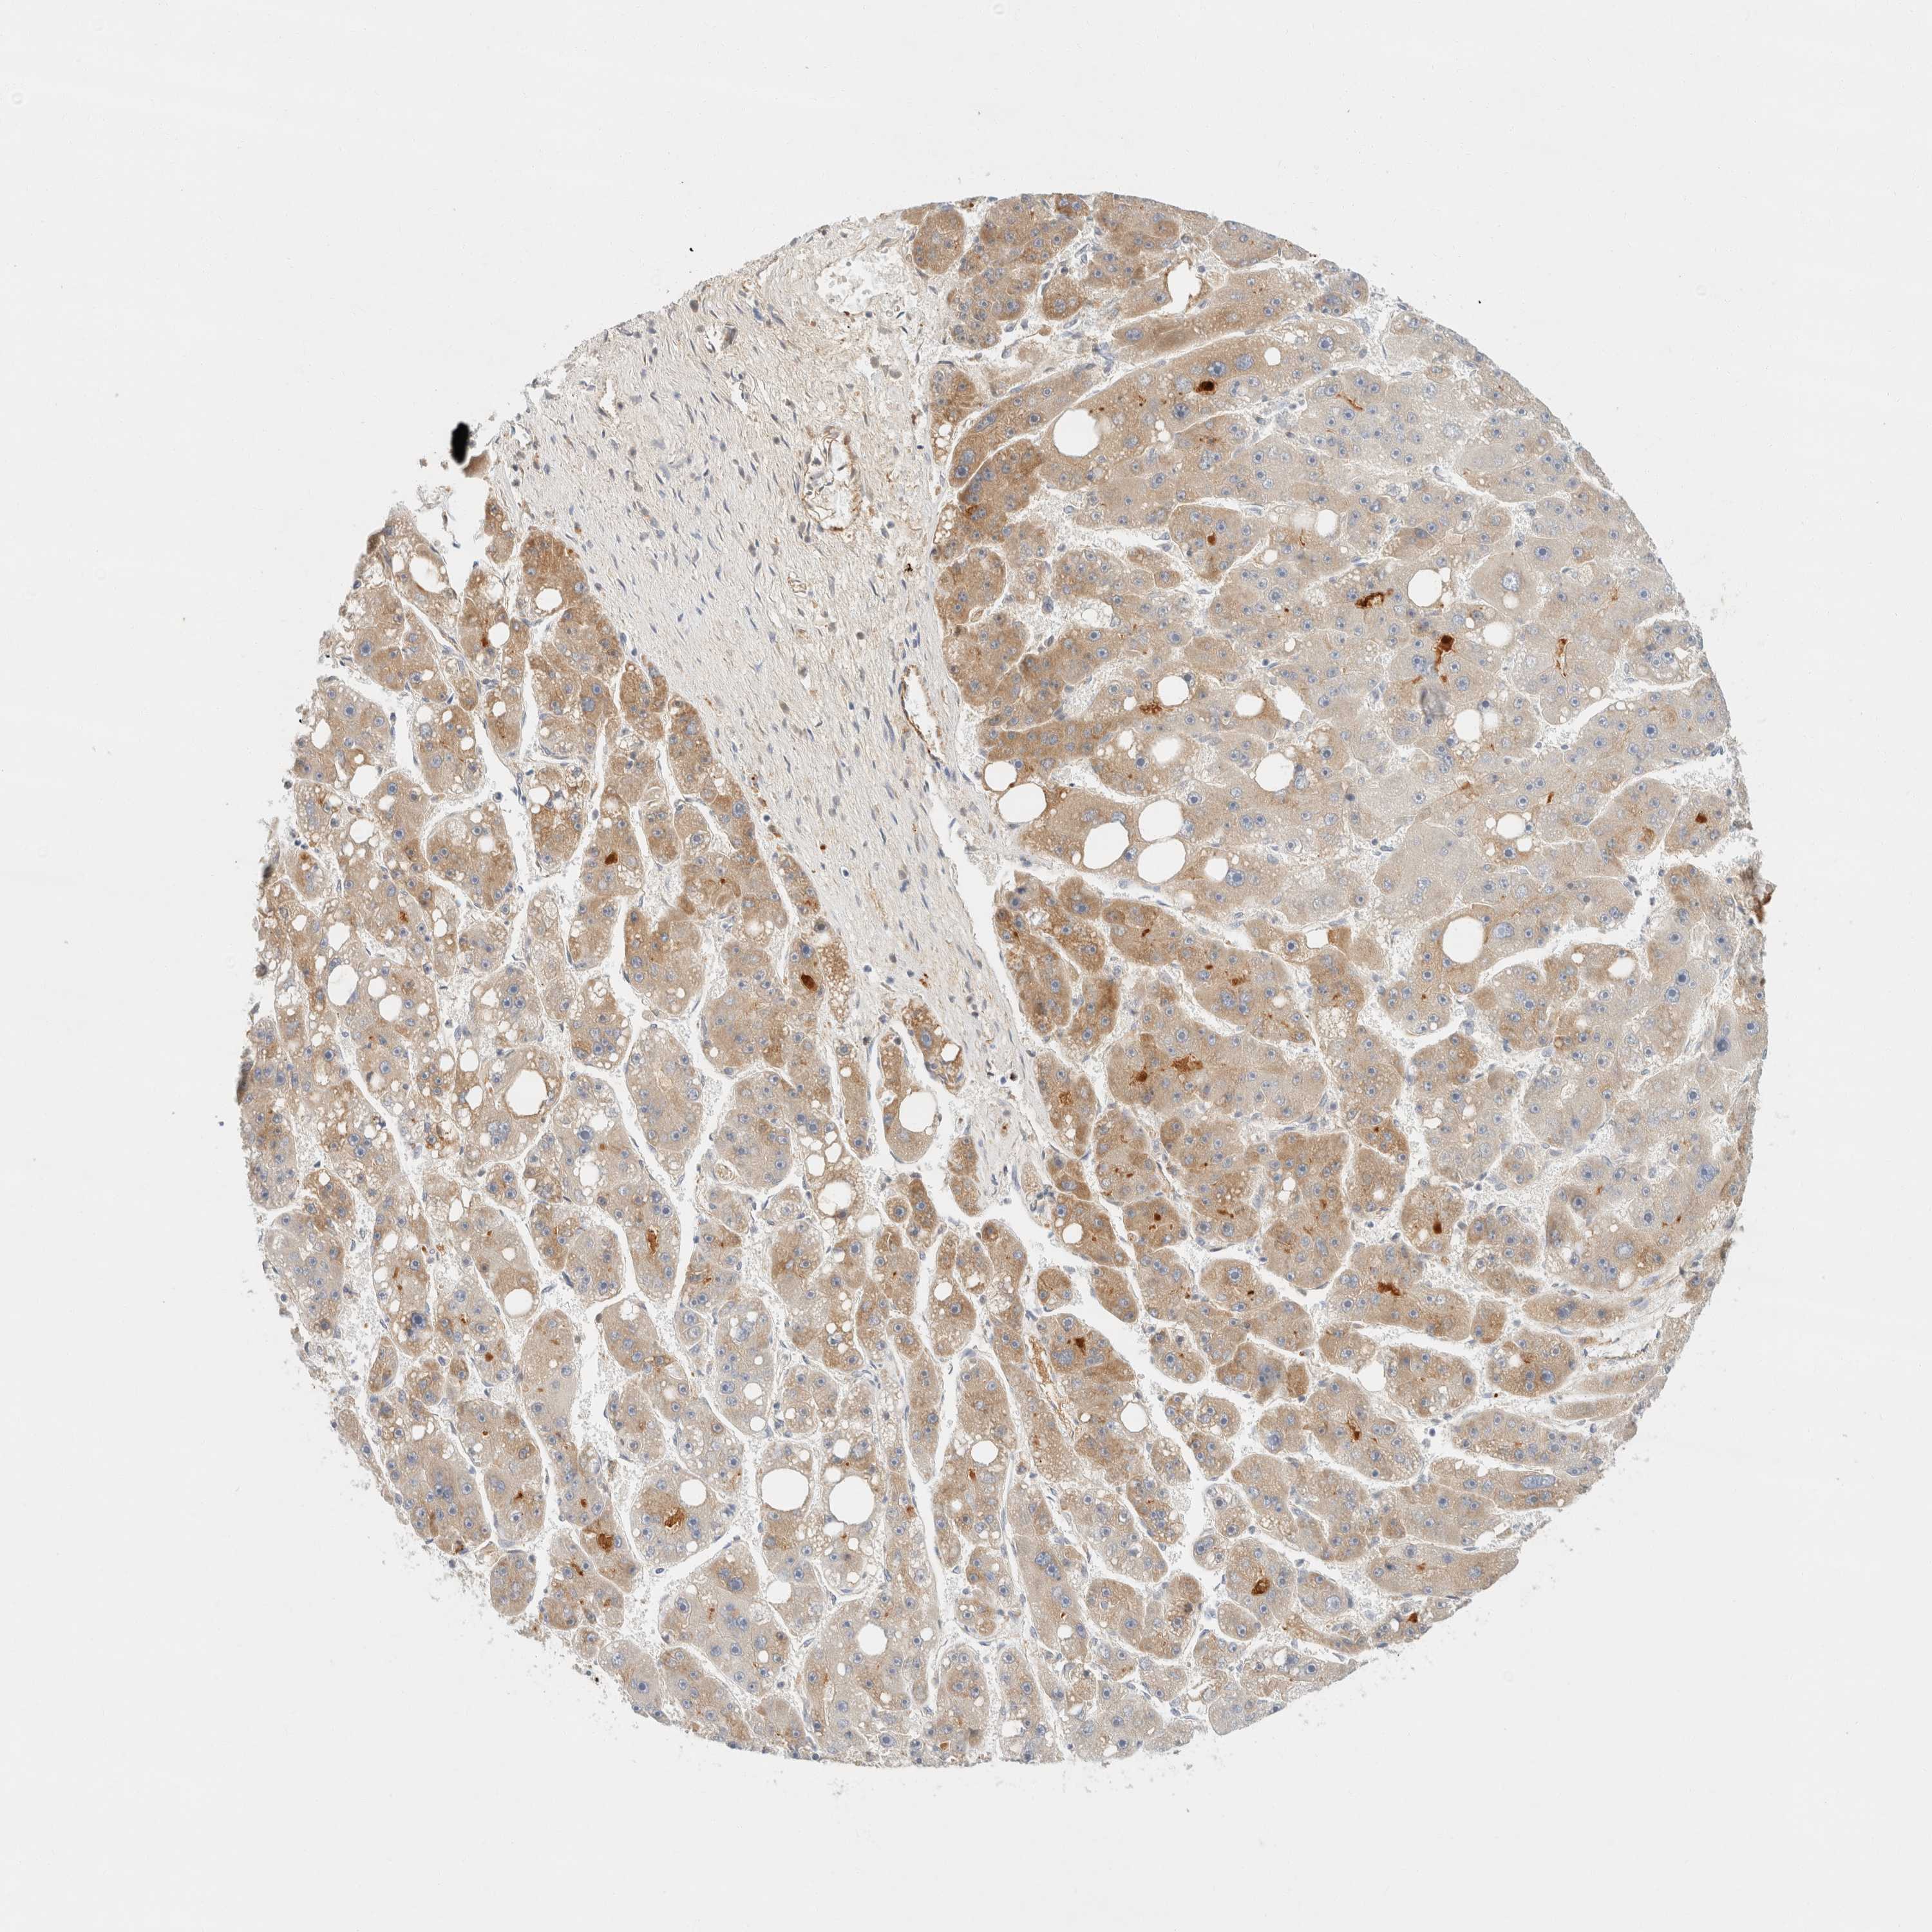

LIVER CANCER - Protein expressioni

A mouse-over function shows sample information and annotation data. Click on an image to view it in a full screen mode. Samples can be filtered based on level of antibody staining by selecting one or several of the following categories: high, medium, low and not detected. The assay and annotation is described here.

Note that samples used for immunohistochemistry by the Human Protein Atlas do not correspond to samples in the TCGA dataset.

Antibody stainingi

Antibody staining in the annotated cell types in the current human tissue is reported as not detected, low, medium, or high, based on conventional immunohistochemistry profiling in selected tissues. This score is based on the combination of the staining intensity and fraction of stained cells.

Each image is clickable and will lead to virtual microscopy that enables deeper exploration of all samples and also displays staining intensity scores, fraction scores and subcellular localization as well as patient and tissue information for each sample.

Antibody HPA023694

Staining

High

Medium

Low

Not detected

Intensity

Strong

Moderate

Weak

Negative

Quantity

>75%

75%-25%

<25%

None

Location

Nuclear

Cytoplasmic/membranous

Cytoplasmic/membranous,nuclear

Cholangiocarcinoma

Carcinoma, Hepatocellular, NOS